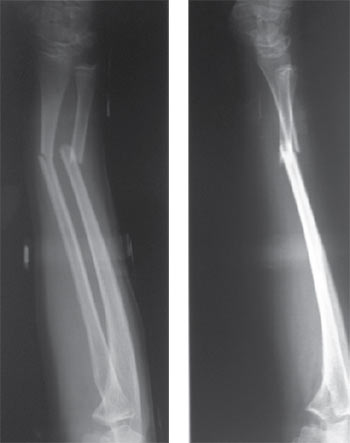

Mujer de 26 años con cuadro clínico consistente en múltiples fracturas a lo largo de su vida con inicio a los 17 meses de edad con fractura de fémur izquierdo y refractura del mismo a los 4 años de edad (figura 1), posteriormente a los 9 años fractura condílea derecha y a los 10 años fractura radial y cubital izquierda (figura 2), todas con traumas mínimos.

|

| Figura 2. Fractura de radio y cúbito izquierdos |